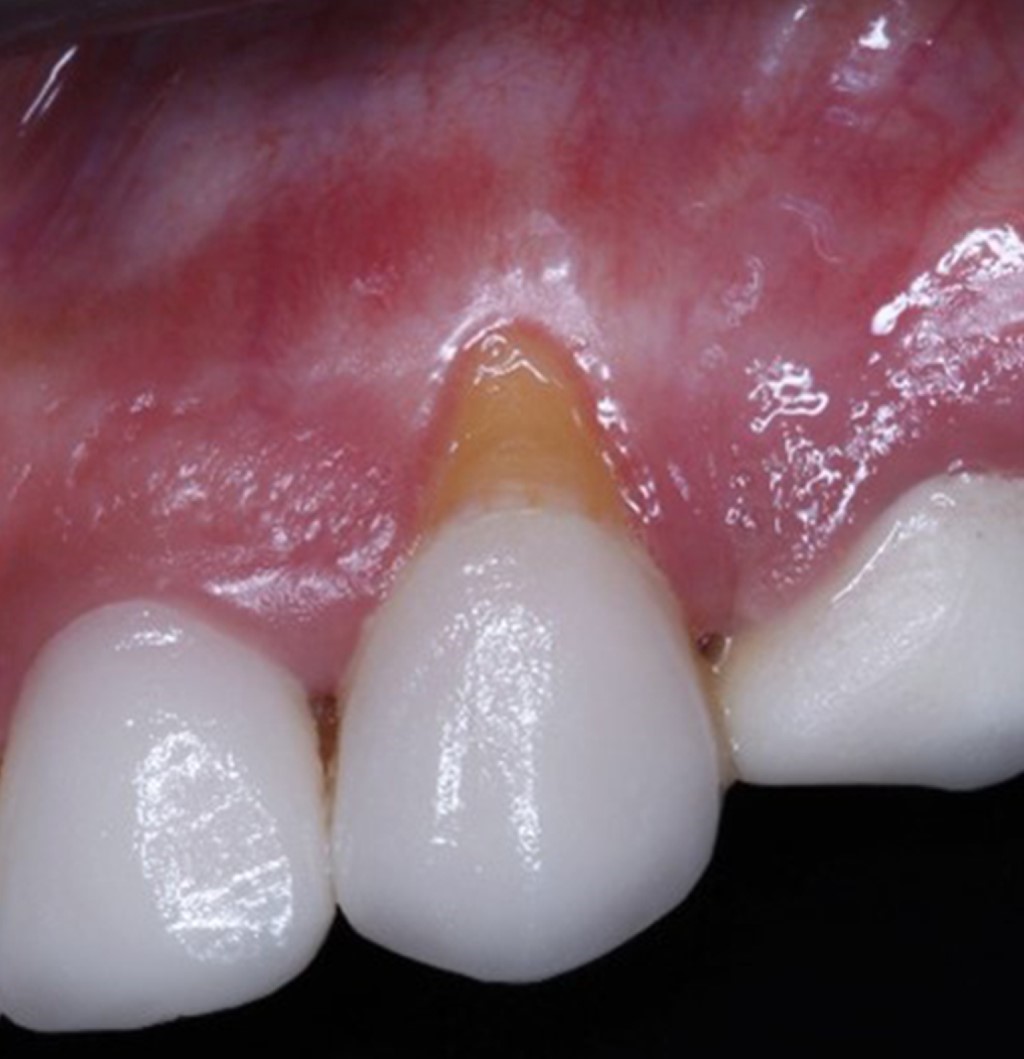

Clínicamente, se presenta una recesión gingival de 4 mm de longitud en el canino superior izquierdo (diente 23), la cual se formó después de 14 días posteriores a la cementación adhesiva de una carilla de porcelana feldespática; se observa un fenotipo gingival fino, 2 mm de tejido gingival queratinizado, y profundidad al sondeo periodontal no mayor a 2 mm, sin pérdida de inserción interproximal (Figura 2).

La recesión gingival fue clasificada como tipo I de Cairo. Se optó por realizar la cobertura radicular mediante la técnica de colgajo de avance coronal e injerto de tejido conectivo subepitelial.

Figura 2